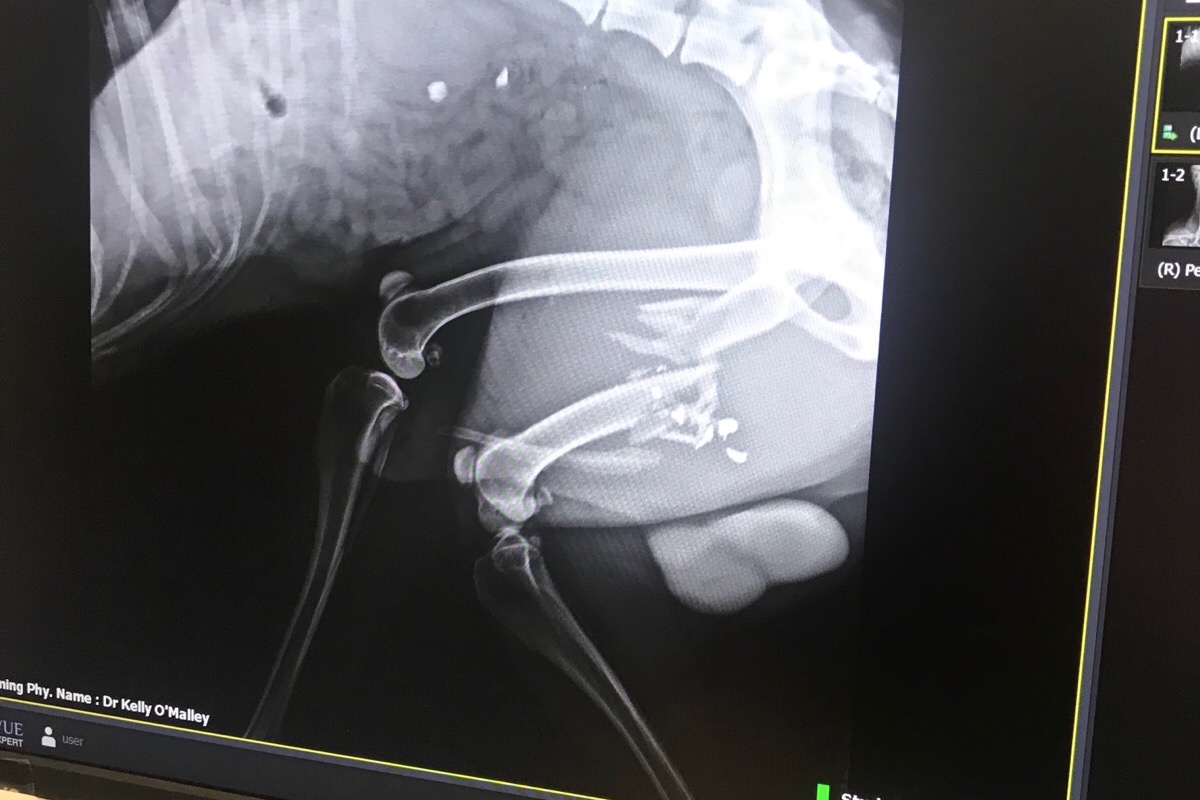

Saturday morning he went for a run and found himself in the sights of a high powered rifle. For some reason, I don’t know, someone shot him. He’s never been aggressive, he doesn’t go near livestock, and is always friendly to other people and pets. He couldn’t have been far from home because he drug himself back. We thought he had been hit by a car and rushed him to the emergency vet where they found the 22 hollow point bullet that shattered his femur. There was nothing they could do there so now we had to wait to see our normal vet. Dr. Lutz Harfs at Animal Medical Services told us that the only way to repair this was to surgically put a steal plate in and we needed to go see a specialist in Spokane because no one in town did this type of operation. Amputation is not a good option because he is such a large dog and large dogs use their hind legs to get up, down, and all around. It could really affect his life expectancy....